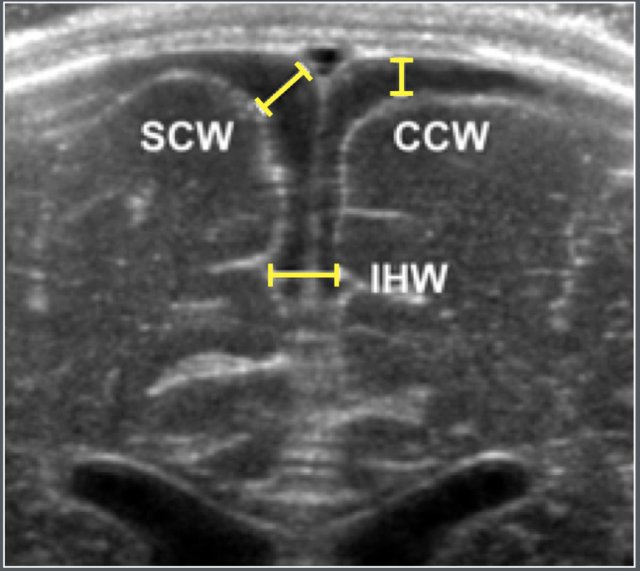

The subarachnoid space was assessed using ultrasonography in 278 full-term healthy Chinese infants. Measurements were taken in the coronal plane at the level of the foramen of Monro (figures)

Ultrasonographic coronal representation of the subarchnoid space at the level of the foramen of Monro.

• SCW = Sino Cortical Width

• CCW = Cranio Cortical Width

• IHW = Inter Hemispherical Width.